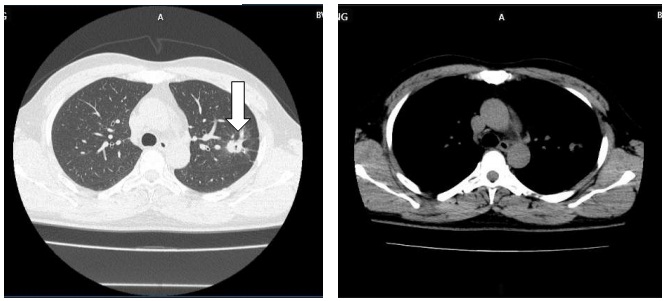

Hình ảnh CT ngực sau 9 tháng điều trị: Khối u phổi phải tiếp tục giảm kích thước 16x19mm (mũi tên màu trắng). Không còn hạch rốn phổi.

Sau 9 tháng điều trị: U phổi giảm kích thước, hạch trung thất không còn, tổn thương di căn não đơn ổ biến mất, chất chỉ điểm khối u CEA, Cyfra 21-1 giảm về giới hạn bình thường. Bệnh nhân không gặp tác dụng phụ đáng kể nào trong quá trình điều trị.